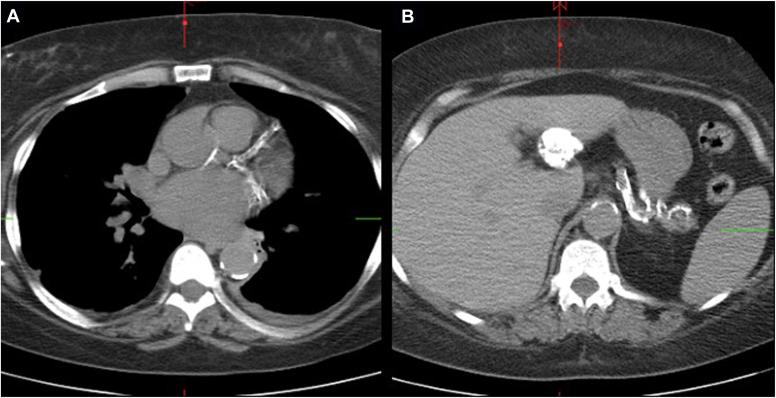

A 48-year-old woman with a history of hypertension, coronary artery disease, and ESRD on hemodialysis presented with severe secondary hyperparathyroidism and calciphylaxis. She had significant changes to her face in the last 3 months leading to oropharyngeal dysphagia and difficulty articulating. Physical examination revealed bony overgrowth in her upper jaw and hard palate, widely spaced teeth, and calcinosis cutis. Her parathyroid hormone (PTH), calcium, and phosphorus levels were 5066 pg/mL (normal range, 12-88 pg/mL); 10.0 mg/dL (8.4-10.2 mg/dL); and 5.4 mg/dL (2.7-4.5 mg/dL); respectively. Using a multidisciplinary approach, she successfully underwent a 3.5-gland parathyroidectomy (immediate postoperative PTH level, 600 pg/mL). She was discharged without complication. Pathology showed hypercellular parathyroid glands with reactive changes.

一名48岁女性,有高血压、冠状动脉疾病史,因ESRD接受血液透析治疗,出现严重继发性甲状旁腺功能亢进和钙化防御。在过去3个月里,她的面部发生了显著变化,导致口咽吞咽困难和言语不清。体格检查发现其上颌骨和硬腭骨质过度生长、牙齿间距增宽以及皮肤钙化。她的甲状旁腺激素(PTH)、钙和磷水平分别为5066 pg/mL(正常范围12 - 88 pg/mL)、10.0 mg/dL(8.4 - 10.2 mg/dL)和5.4 mg/dL(2.7 - 4.5 mg/dL)。采用多学科方法,她成功接受了3.5枚甲状旁腺切除术(术后即刻PTH水平为600 pg/mL)。她出院时无并发症。病理检查显示甲状旁腺细胞增多并伴有反应性改变。